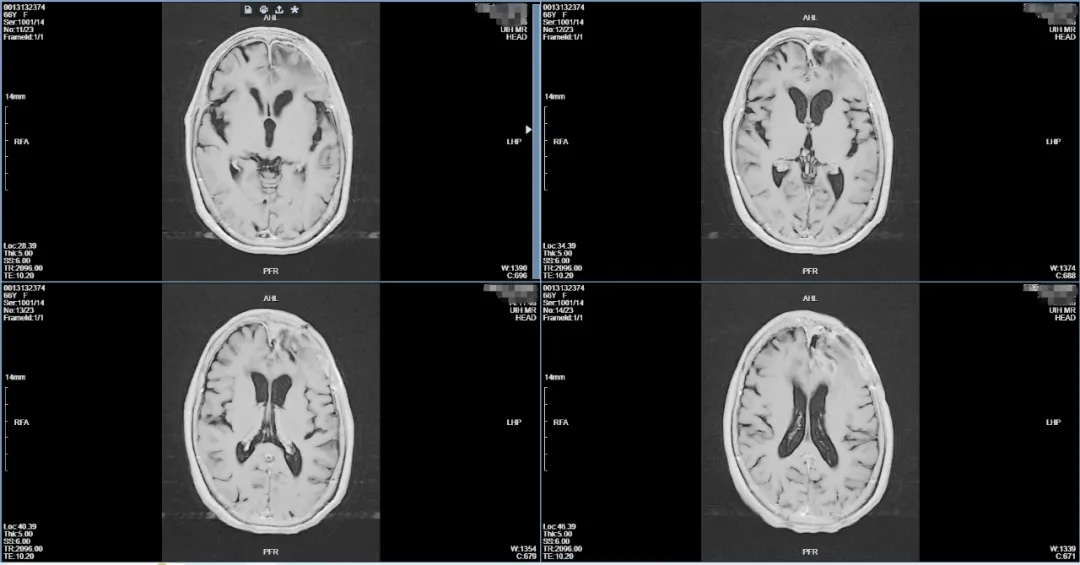

▲术后复查肿瘤全切,脑结构恢复正常

术后吴阿姨恢复良好,无言语功能障碍及偏瘫,患者及家属对手术结果非常满意。